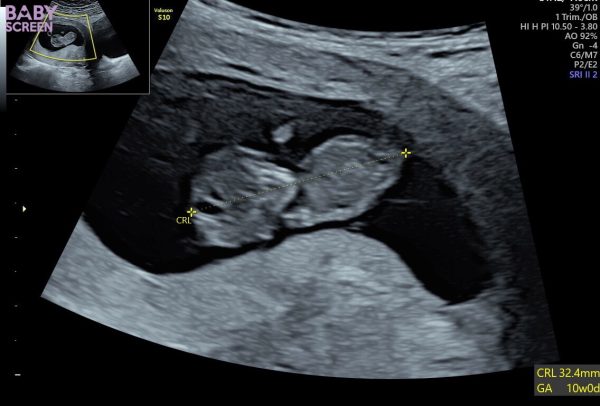

Idag gjorde Ida ett ultraljud. Lilla bebisen har allt ❤️ ett hjärta som slår, armar och ben och massor av energi. Eftersom inte barnets pappa vill ta del av sitt barn och uppleva allt det fantastiska kring graviditeten så ställer Idas bästa vän Diona upp med kärlek, glädje och inspiration ❤️

Beräknad förlossning är 19 maj nästa år ❤️ ser fram emot det!